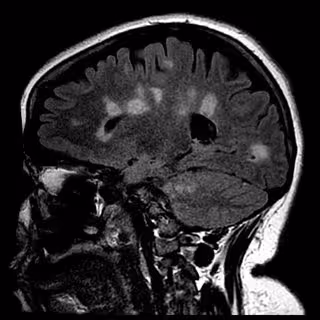

Cicatrización del cerebro en la esclerosis múltiple - UNIVERSITY OF BRITISH COLUMBIA - Archivo

Investigaciones anteriores han demostrado que una región cerebral llamada córtex se reduce con el tiempo en pacientes con EM, un proceso conocido como atrofia cortical. Los procesos que impulsan esta contracción cortical, hasta ahora, no han sido aclarados.

En personas sanas, estas neuronas de proyección están involucradas en la comunicación de información entre diferentes áreas del cerebro. Por lo tanto, es posible que el daño a estas células pueda afectar las capacidades cognitivas en pacientes con EM. Además, la pérdida de este tipo de células en particular ayuda a explicar por qué los cerebros de los pacientes con EM se reducen con el tiempo: cuantas más células se dañan y pierden, menos espacio ocupa el cerebro.